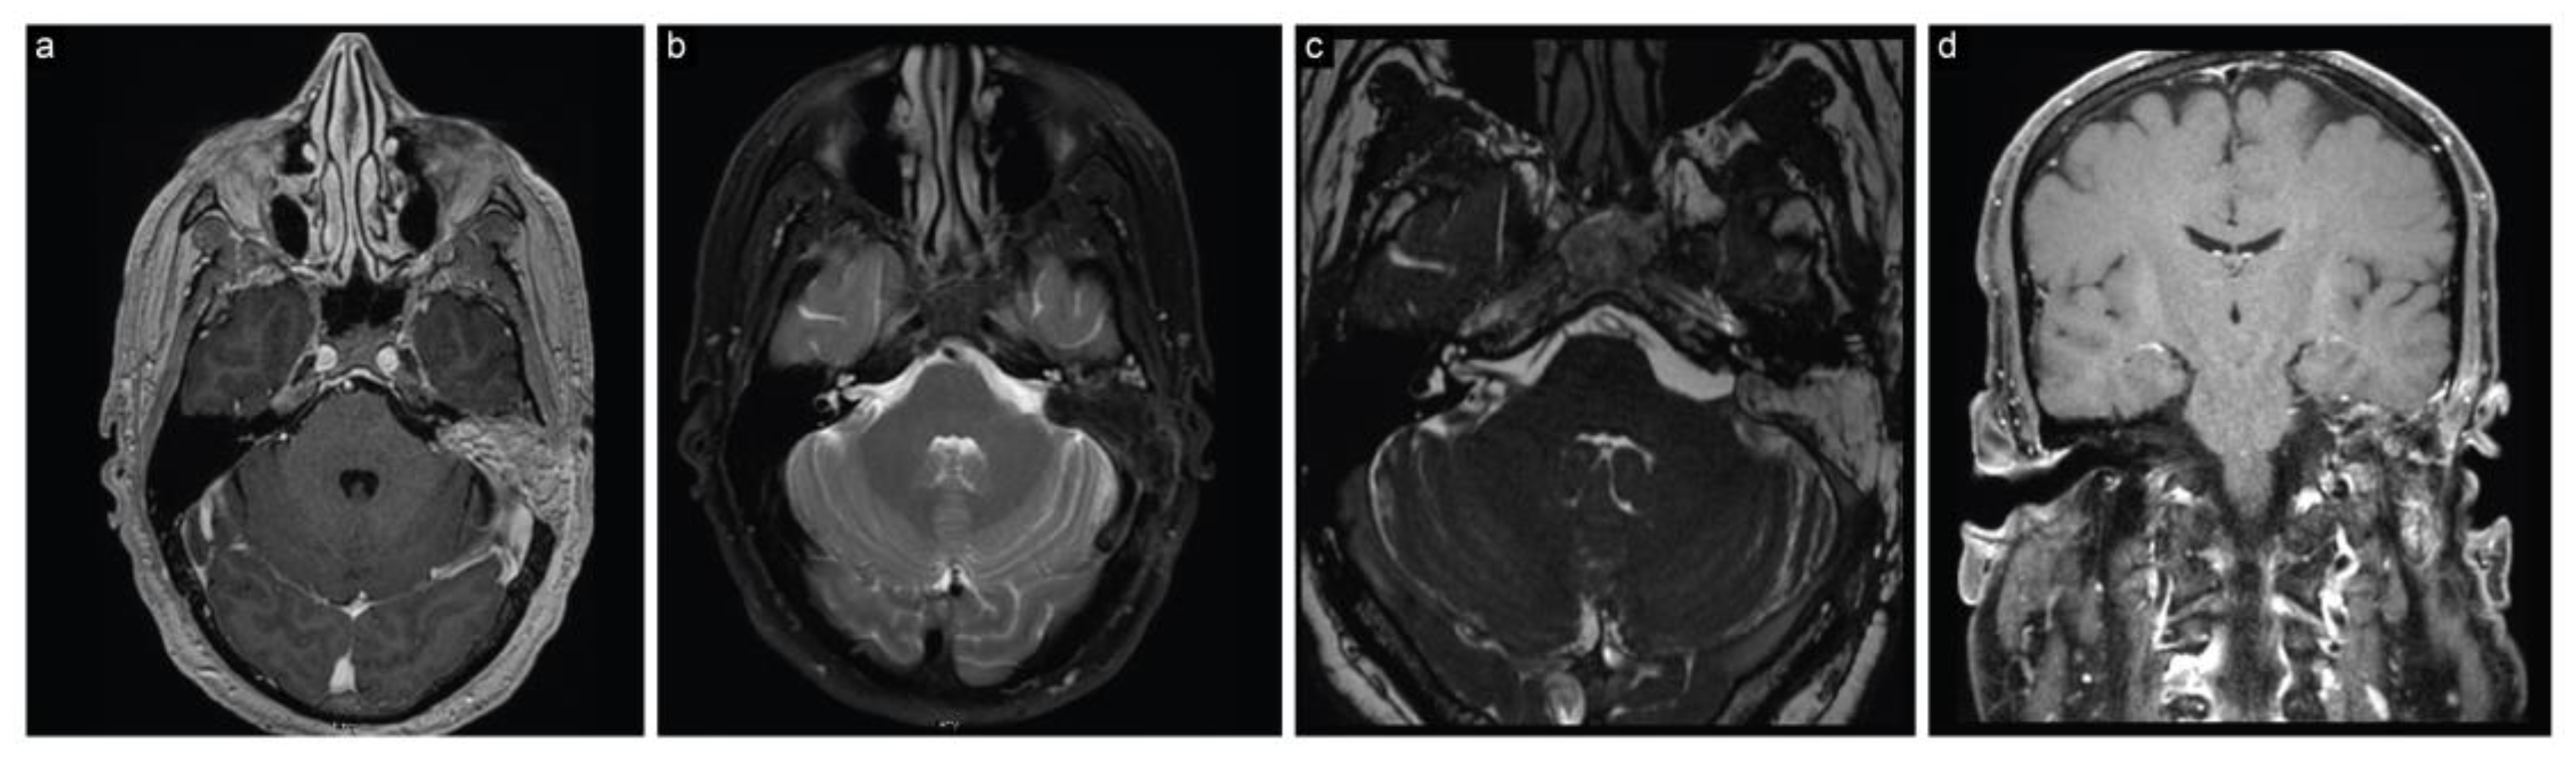

The second case is a 48-year-old man who had presented with dizziness and numbness on the left side of his face for the past six weeks. These symptoms had been escalating, and were accompanied by a severe, newly developed headache. An MRI scan revealed a large cystic left cerebellopontine angle lesion (4.1 cm × 2.5 cm × 2.8 cm), suggestive of a VS, along with signs of recent hemorrhage within the lesion (Figure 4). An initial audiogram revealed moderate to severe sensorineural hearing loss, with no serviceable hearing on the left side.

Figure 4.

Case 2 preoperative neuroimaging. (a) Axial T1-weighted postcontrast, (b) axial T2-weighted, (c) coronal T1-weighted postcontrast, and (d) coronal T2 FLAIR MRI scans show a large cystic CPA lesion, suggesting a vestibular schwannoma along with recent intratumoral hemorrhage.